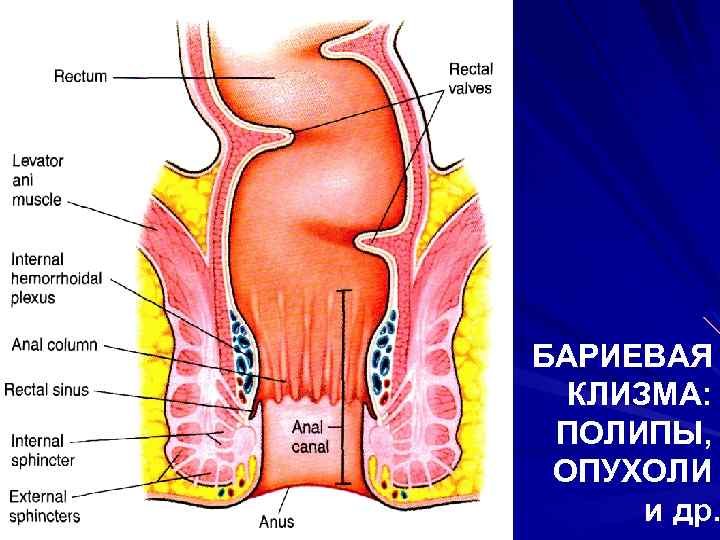

РАК ТОЛСТОЙ КИШКИ

РАК ТОЛСТОЙ КИШКИ

РАК ТОЛСТОЙ КИШКИ

РАК ТОЛСТОЙ КИШКИ

БАРИЕВАЯ КЛИЗМА: ПОЛИПЫ, ОПУХОЛИ и др.

БАРИЕВАЯ КЛИЗМА: ПОЛИПЫ, ОПУХОЛИ и др.